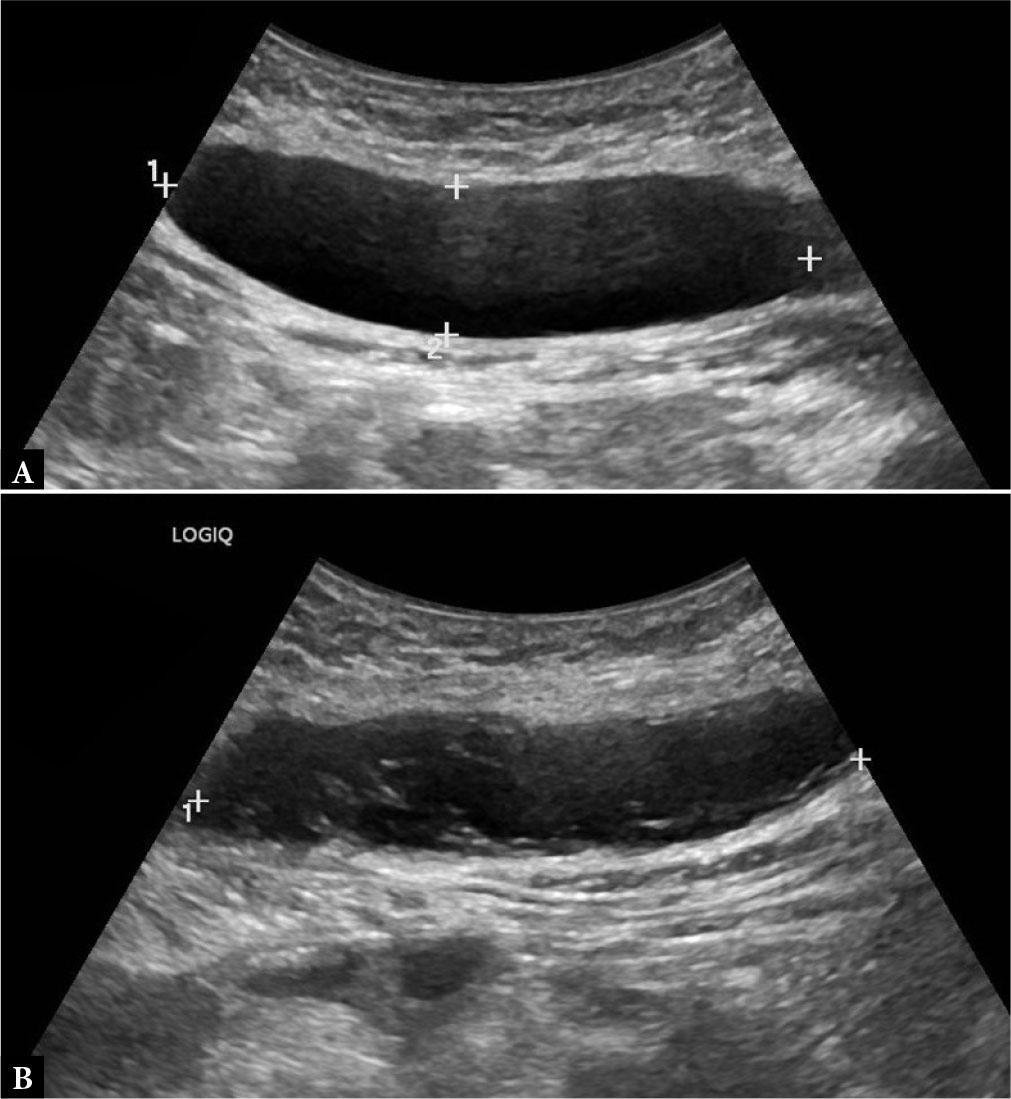

Given the mechanism of injury and clinical findings, a US examination was performed, revealing an intramuscular hematoma within the right rectus femoris muscle. Serial US evaluations were performed within a month of each other to monitor the evolution of the post-traumatic hematoma. Over time, progressive reduction in size was observed, along with changes in echotexture consistent with hematoma resorption. No significant vascular signal was detected on CD examination. However, the patient reported a difference in muscle strength in the right leg. Comparative imaging revealed hypotrophy and increased echotextural inhomogeneity of the right rectus femoris compared with the contralateral side, consistent with evolving post-traumatic muscle remodeling and potential disuse atrophy (Fig. 3).

Ultrasound of the right rectus femoris muscle showing a heterogeneous hypoechoic lesion (1.2 × 1.6 × 2.7 cm) without internal flow on CD (A). Follow-up examinations at one (B) and four weeks (C) demonstrate progressive reduction in size (from 1.2 × 1.3 × 1 cm to 1.3 × 0.5 cm) and increasing echogenicity, consistent with resorptive hematoma evolution. Mild subcutaneous tissue edema persisted throughout the follow-up period. Comparative imaging (D) highlights muscle asymmetry and echotextural inhomogeneity, suggestive of evolving structural remodeling

Educational tip: When assessing muscle trauma, always scan from origin to insertion in both longitudinal and transverse planes. Monitor the echogenic evolution of hematomas over time, typically progressing from hypoechoic (acute phase) to echogenic (chronic/ resorptive phase). Pay close attention to secondary signs such as muscle hypotrophy or asymmetry, especially during later follow-ups, as these may reflect disuse or incomplete functional recovery.

Clinical correlation: Post-traumatic hematomas follow a predictable course unless complicated. Progressive healing (size reduction, increasing echogenicity) supports a conservative approach. However, persistent asymmetry, altered echotexture, or strength deficits may indicate delayed functional recovery or evolving fibrosis. Such findings justify a personalized rehabilitation strategy and continued imaging surveillance in selected cases.